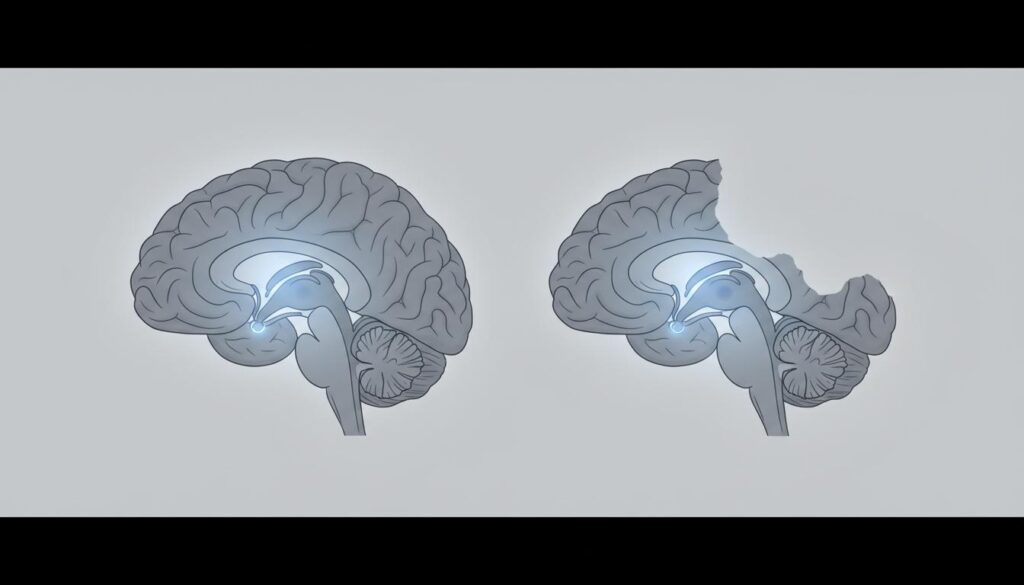

הקורפוס קלוסום, המכונה גם "כפיס המוח", הוא צרור סיבים עצביים שמחבר בין שתי ההמיספרות של המוח. אפשר לדמו אותו לגשר תקשורת מורכב. הוא מכיל כ-200 מיליון סיבים עצביים ולכן זהו אחד המבנים המרכזיים שמאפשר לשני צידי המוח לתקשר ולתאם פעולות.

התפקיד המרכזי שלו הוא העברת מידע בין צידי המוח, תיאום תנועות, שיתוף חושי, ואינטגרציה של מידע מורכב. בלעדיו, כל המיספרה עובדת לבד ללא תיאום עם האחרת, מה שמשפיע כמעט על כל תחום התפתחותי.

במקרים של היעדר קורפוס קלוסום באופן מלא, לא קיים בכלל גשר התקשורת בין ההמיספרות. הדבר דומה לשני מחשבים ללא חיבור ביניהם. כל אחד עובד בנפרד, מה שמוביל לקשיים משמעותיים בתיאום ובאינטגרציה של מידע.